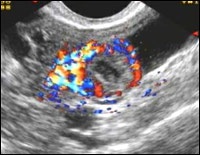

În primele zile după ovulație în jurul corpului galben este format rețea vasculară densă formată din mai multe straturi, în special pronunțată în faza de înflorire. In dopplerograms de culoare în jurul luteum apare pronunțat inel de culoare (fig. 17-19), în care fluxul de sânge are viteză mare și impedanță scăzută (Fig. 20). Acest lucru este tipic neovascularizării fiziologice turbulente.

corpus luteum Blossom.

Doppler color.

Perioada de glorie a corpului galben.

Doppler color.

Perioada de glorie a corpului galben.

Putere Doppler.

Doppler infloreste corp galben.

IR de înaltă și joasă MAS.